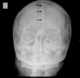

The occipital bone () is a cranial dermal bone and the main bone of the occiput (back and lower part of the skull). It is trapezoidal in shape and curved on itself like a shallow dish. [Source: Wikipedia ]